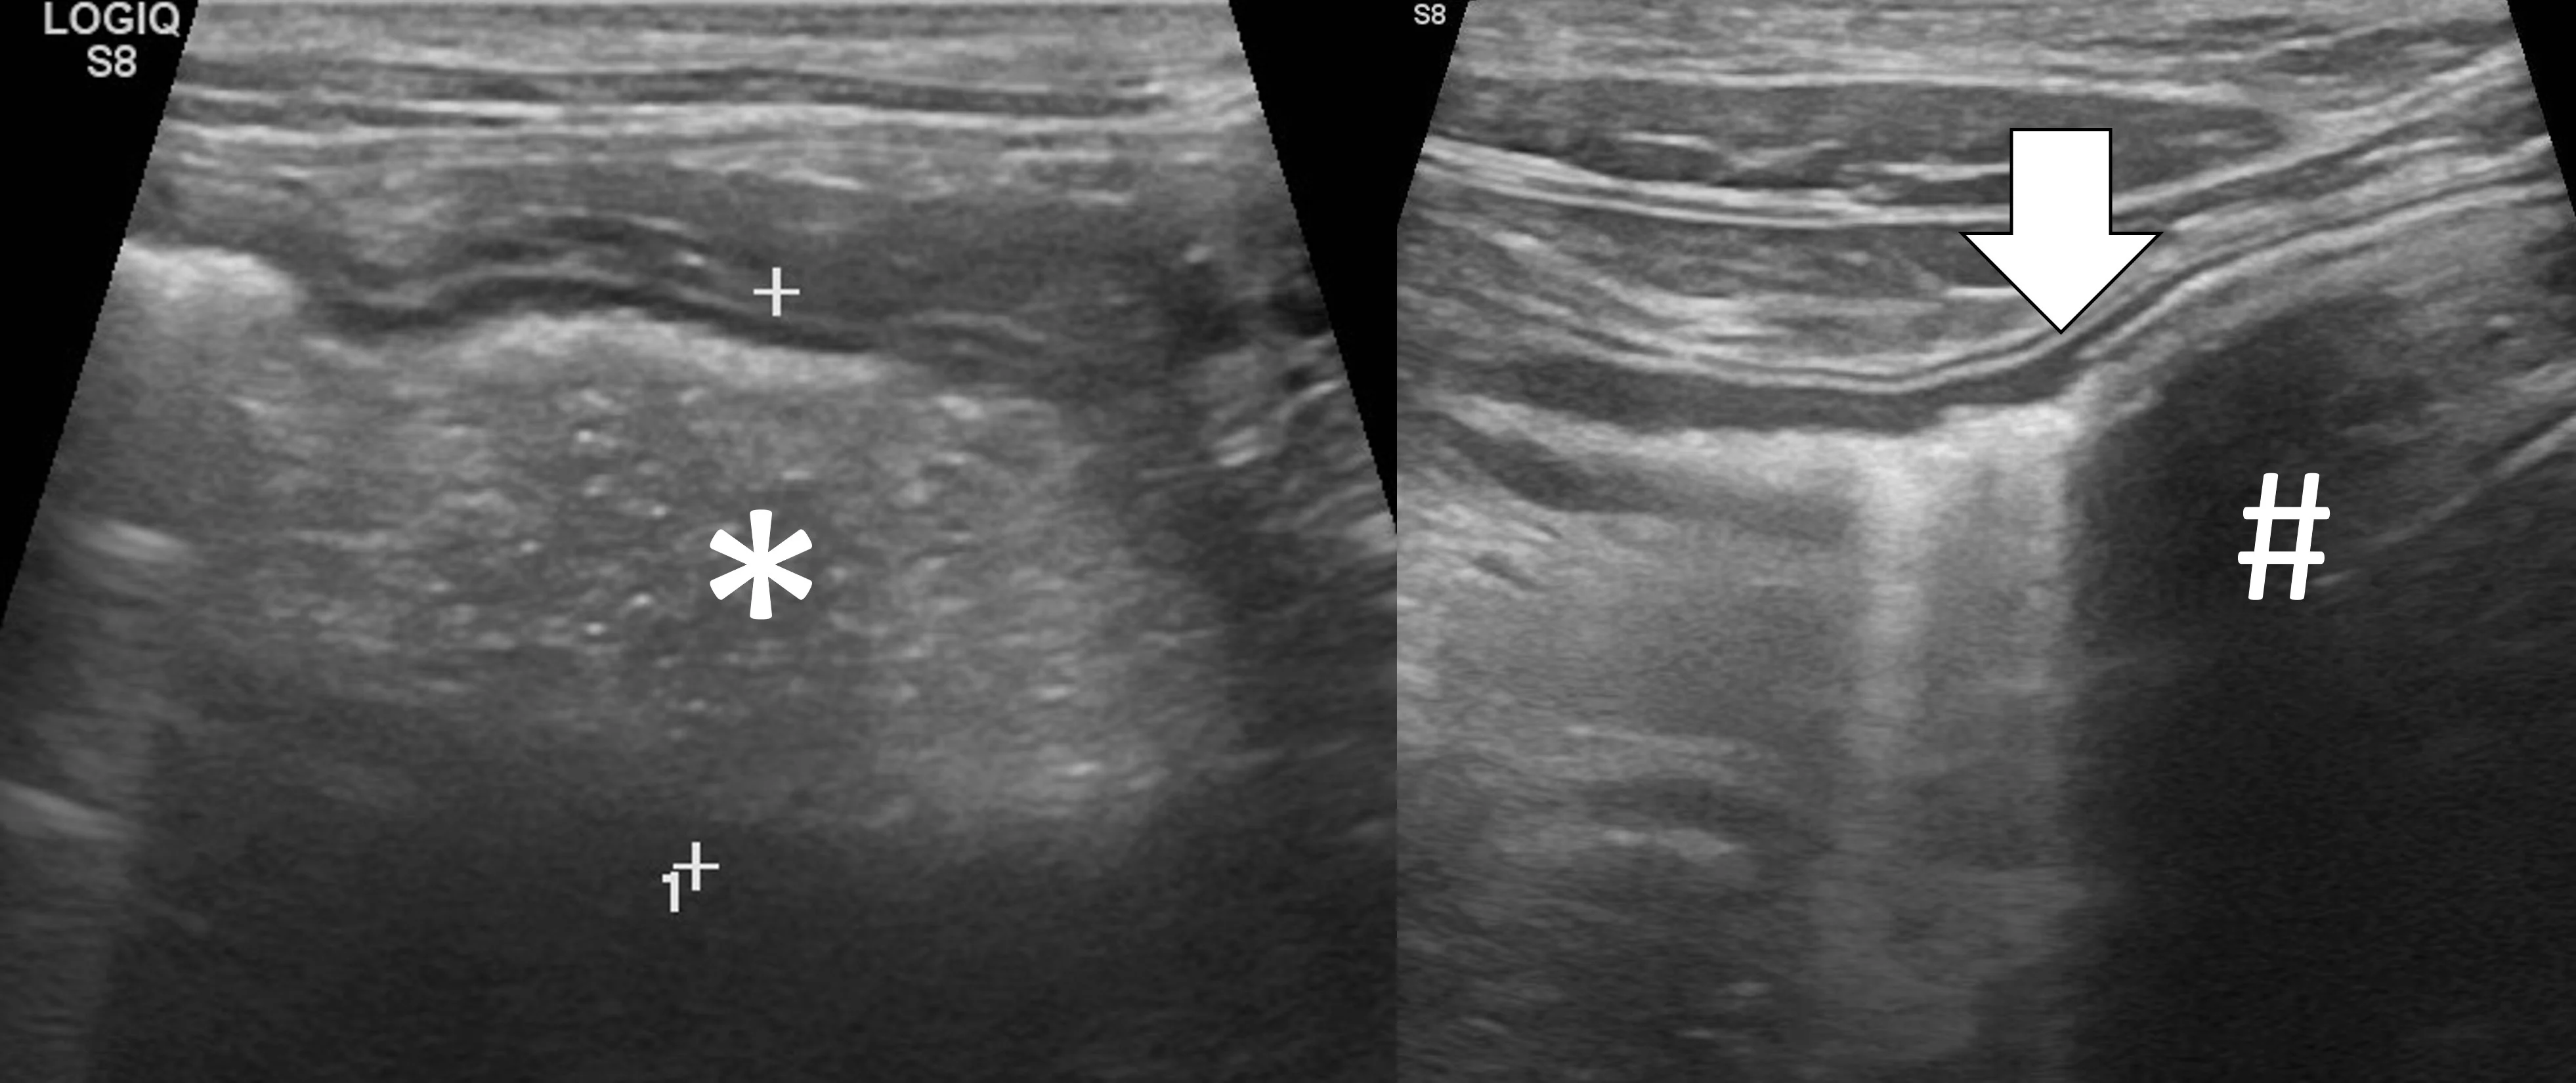

Linear foreign body obstructions occur when an object (eg, string, cloth) becomes stuck orally but extends aborally through the intestinal tract. Peristaltic contractions typically cause the small intestine to travel orally, eventually bunching. As a result, ultrasonographic findings include intestinal bunching (ie, plication) with or without a hyperechoic linear structure coursing through the lumen of the affected bowel (Figure 4).9-12 In some cases, trapped gas can cause a line that can be mistaken for the linear foreign body. Plication should not be confused with normal peristalsis or corrugation (Figure 5). With corrugation, the serosal margin is normal, and the mucosa and submucosa are undulant; with plication, the serosal margin is affected.14 In chronic cases, the mesentery surrounding the affected bowel may become hyperechoic, which can help identify the site of obstruction. Sterile inflammation and transudation may then result in focal accumulation of a small volume of free fluid. Mesenteric changes and peritoneal effusion also increase concern for bowel rupture and septic peritonitis. Patients may have concurrent findings of pyloric outflow or small intestinal mechanical obstruction, depending on the size and nature of the ingested cloth or string.

Abdominal ultrasound of an 11-month-old neutered male domestic shorthair cat with a surgically confirmed toy ball connected to a linear foreign body anchored in the pylorus (asterisk). The proximal duodenum is plicated (black arrows) with a hyperechoic linear structure (white arrows) coursing through the center. Normal small intestine can be seen adjacent to the plicated duodenum (caret).

Abdominal ultrasound of an 8-year-old spayed miniature pincher with inflammatory bowel disease and pancreatitis. The mucosal and submucosal layers of a loop of jejunum are undulating (carets), but the serosal margin remains smooth (arrows).